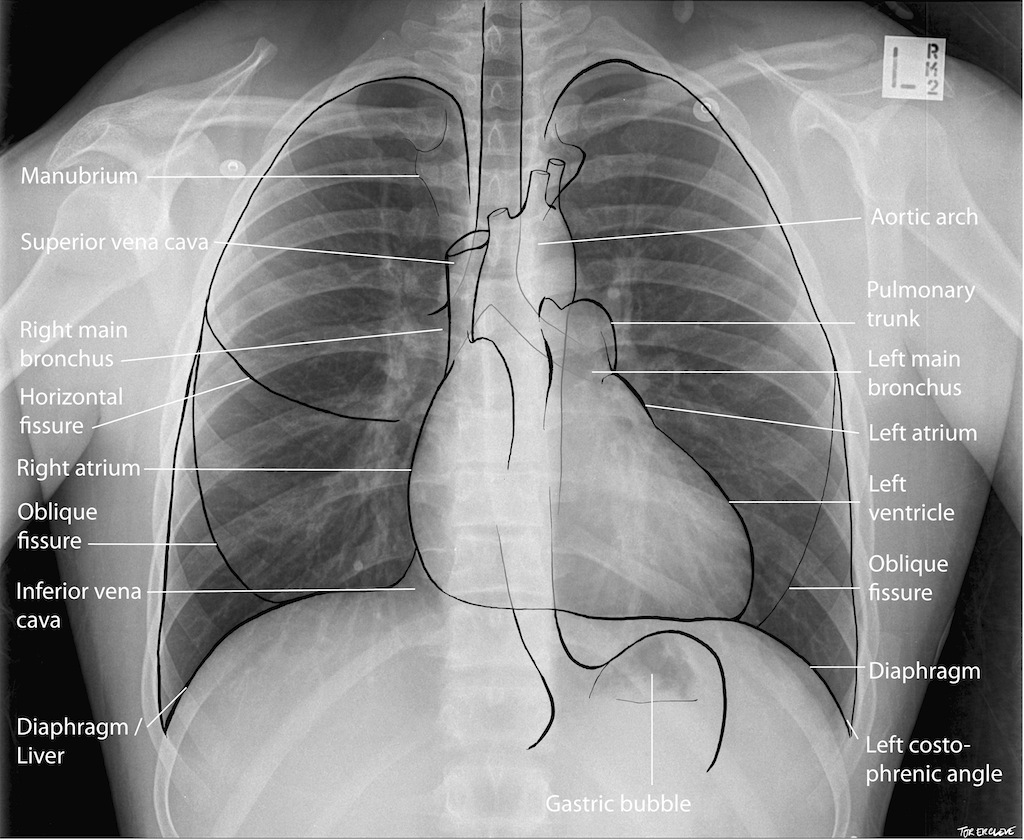

Definition: visceral department in the middle of the thoracic cavity, between right and left pleural cavity

Divisions:

→ dividing plane: “transthorscal plane”, from sternal angle to T4 and T5 vertebral discs